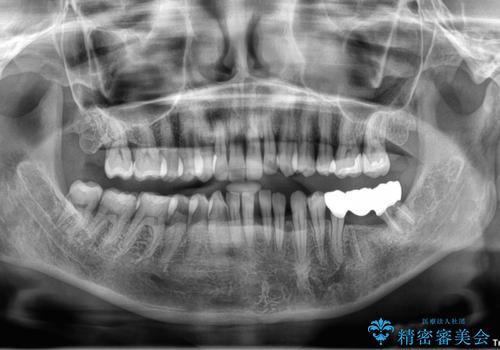

最初にもともとのブリッジを壊し、矯正用の仮歯にかえた上で部分矯正を開始しました。

部分矯正期間はだいたい3か月弱です。

矯正終了後、左下7の近心は再度クリーニングを行っています。

その後ブリッジの製作を行いました。